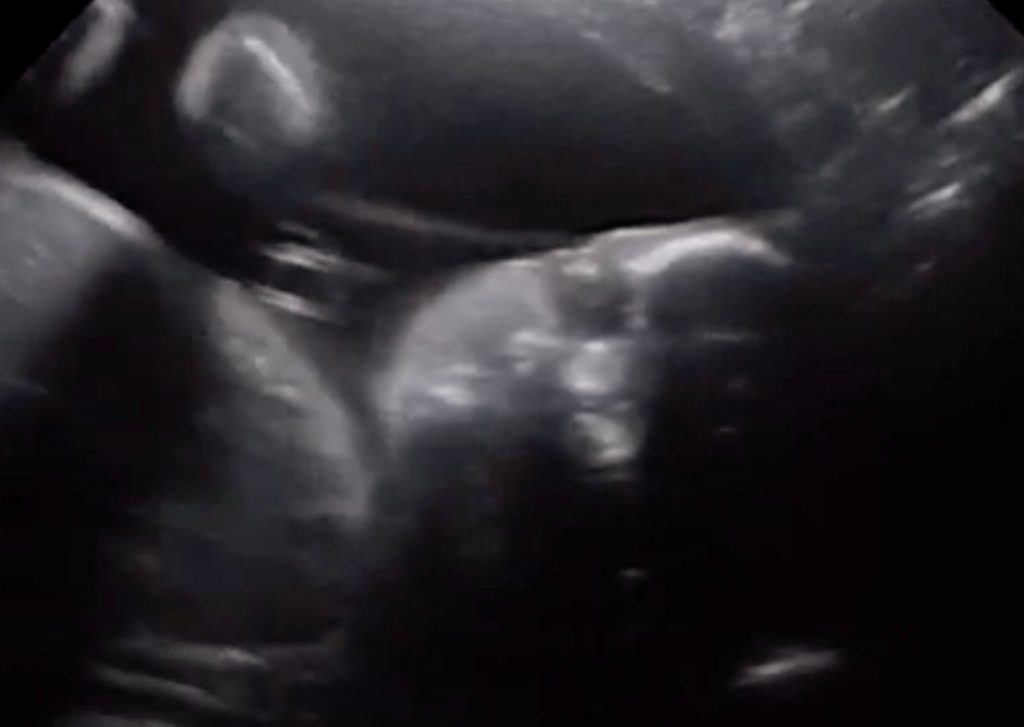

Lucy Bearley tiene 28 semanas de embarazo y junto a su esposo Stuart Barrett, acudieron al médico para realizarse una ecografía de rutina.

El ultrasonido los dejó impactados, ya que el bebé realizó extraños movimientos, donde incluso se le puede ver saludando con su mano derecha y mirándolos: “Afortunadamente, la doctora capturó el momento y efectivamente cuando miramos ahí estaba, no solo saludando sino volteando a mirarnos justo a nosotros”, comentó el padre de la bebé al sitio inglés The Sun